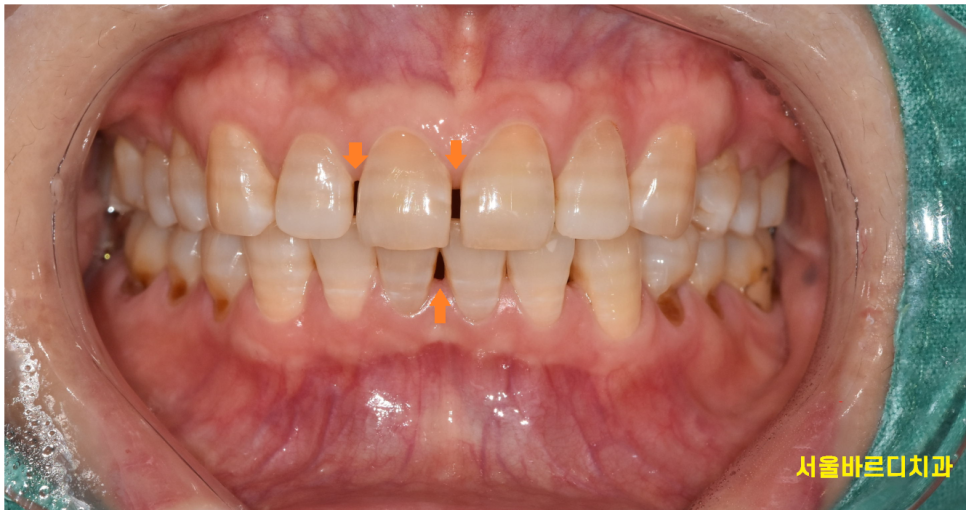

오늘 환자분은 앞니가 전반적으로 다 벌어지셨는데...

공간이 벌어지면 라미네이트를 하기에는 굉장히 유리한 조건입니다!

250220 치아 표면에 오돌토톨하게 붙어있는건 치석이에요~!! 오신김에 스케일링도 진행해드렸답니다.

아래 앞니도 공간이 있긴 하였지만...

다행히 환자분은 웃거나 말할 때

아래 앞니가 입술에 덮여져 잘 안보이셨어요~

우선은 윗니만 라미네이트를 먼저 진행해보고

결과물을 확인하여

나중에 신경쓰이시면 하시라고 말씀드렸죠~~